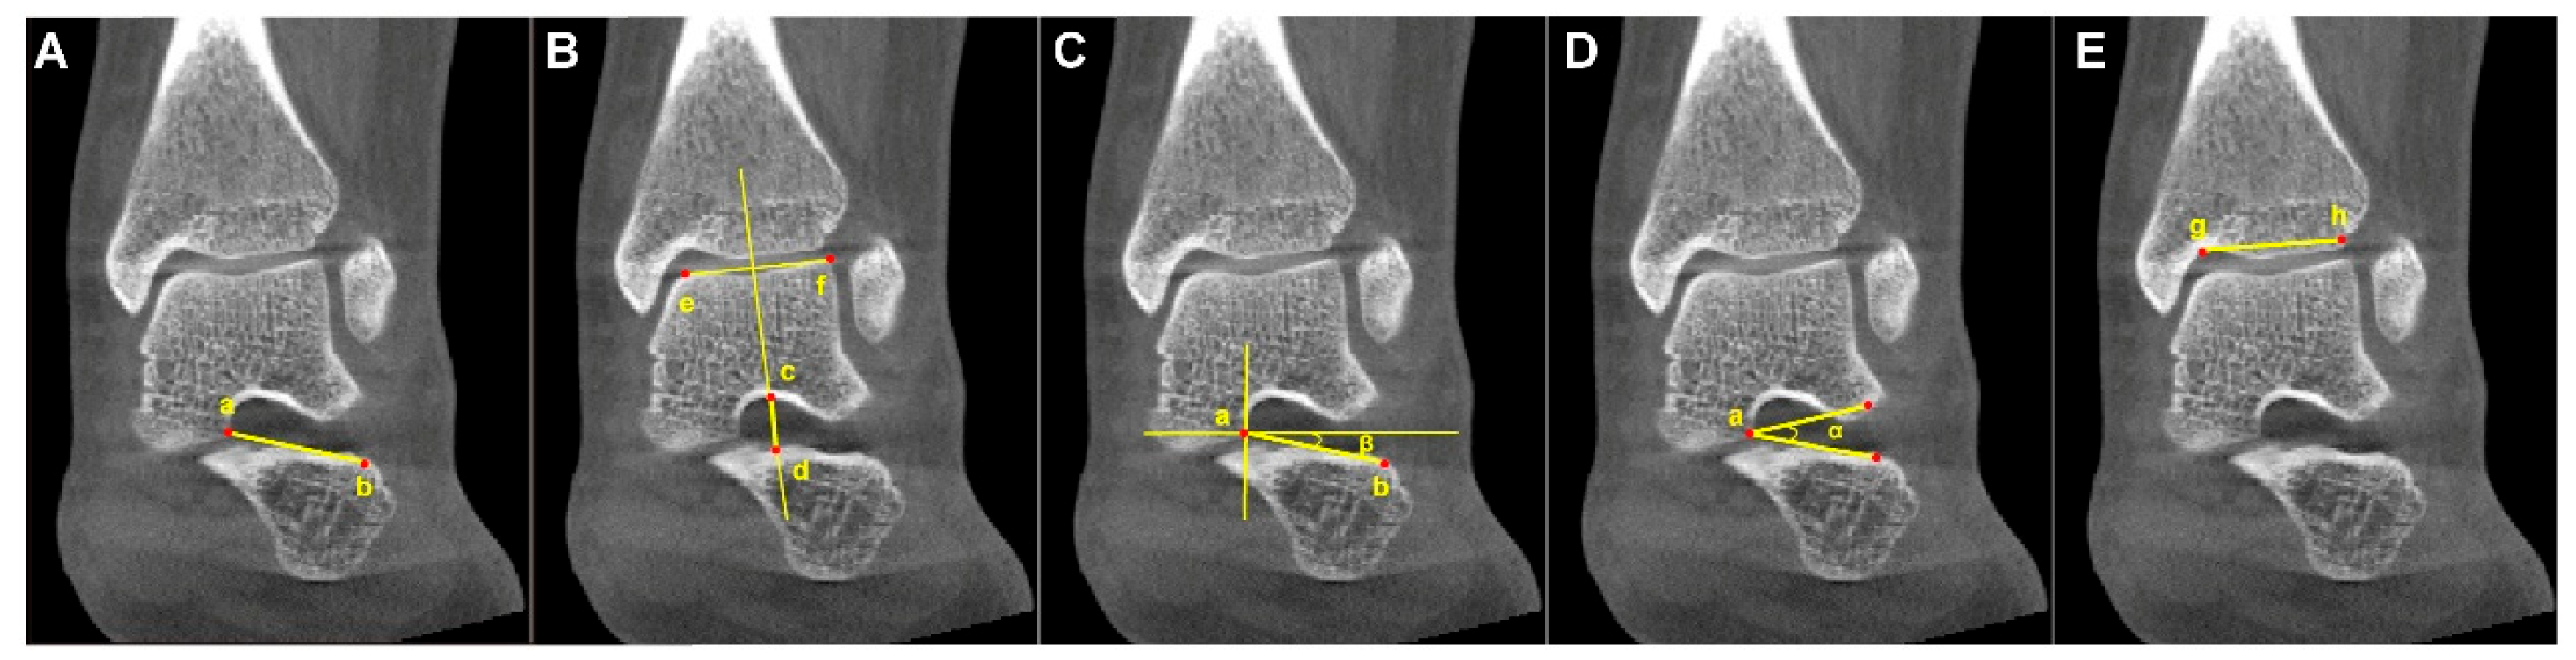

The following parameters were measured: sinus tarsi length (STL), sinus tarsi width (STW), the angle between the long axis of the sinus tarsi and the horizontal line (ST-H angle), the sinus tarsi angle (ST angle), and tibia width. The ratios of STL to tibia width (STL/tibia width) and STW to tibia width (STW/tibia width) were subsequently calculated. The measured parameters were defined as the following and are marked in Figure 3:

Figure 3.

Example diagram of the analyzed parameters from WBCT. (A) Sinus tarsi length (STL): the length between the medial apex (Point a) of the sinus tarsi canal (at the talar edge of the anterior subtalar articular facet) and the inferolateral endpoint (Point b) of the sinus tarsi canal orifice. (B) Sinus tarsi width (STW): the vertical width of the sinus tarsi canal (the length of Line c–d), measured along a perpendicular line passing through the midpoint of Line e–f on the talar surface of the tibiotalar joint, where Point c and Point d denote the intersections of this perpendicular with the superior and inferior borders of the sinus tarsi canal, respectively. (C) The angle between the long axis of the sinus tarsi and the horizontal line (ST–H angle) (β): formed by the long axis of the sinus tarsi canal (Line a–b) and the horizonal line. (D) Sinus tarsi angle (ST angle) (α): formed by the superolateral point and inferolateral point of the sinus tarsi orifice and the medial apex (Point a) of the sinus tarsi canal (i.e., the talar edge of the anterior subtalar articular facet). (E) Tibia width: the length of Line g–h connected the lateral edge (Point g) and the medial turning point (Point h) of the tibial plafond.

- (1)

- Sinus tarsi length (STL): the distance between the medial apex of the sinus tarsi canal (at the talar edge of the anterior subtalar articular facet) and the lateral endpoint of the sinus tarsi canal orifice on the calcaneus.

- (2)

- Sinus tarsi width (STW): the vertical distance between the superior and inferior borders of the sinus tarsi canal, measured along a line perpendicular to the talar surface of the tibiotalar joint, passing through the midpoint of that surface.

- (3)

- Angle between the long axis of the sinus tarsi and the horizontal line (ST-H angle): the angle formed by the line connecting the medial apex of the sinus tarsi canal (at the talar edge of the anterior subtalar articular facet) to the lateral endpoint of the sinus tarsi canal orifice on the calcaneus, and the horizontal line.

- (4)

- Sinus tarsi angle (ST angle): the angle formed by the lateral superior point and lateral inferior point of the sinus tarsi orifice, and the medial apex of the sinus tarsi canal (the talar edge of the anterior subtalar articular facet).

- (5)

- Tibia width: the distance between the lateral edge of the tibial plafond and the medial turning point of the tibia at the tibiotalar joint from an anterior–posterior view.